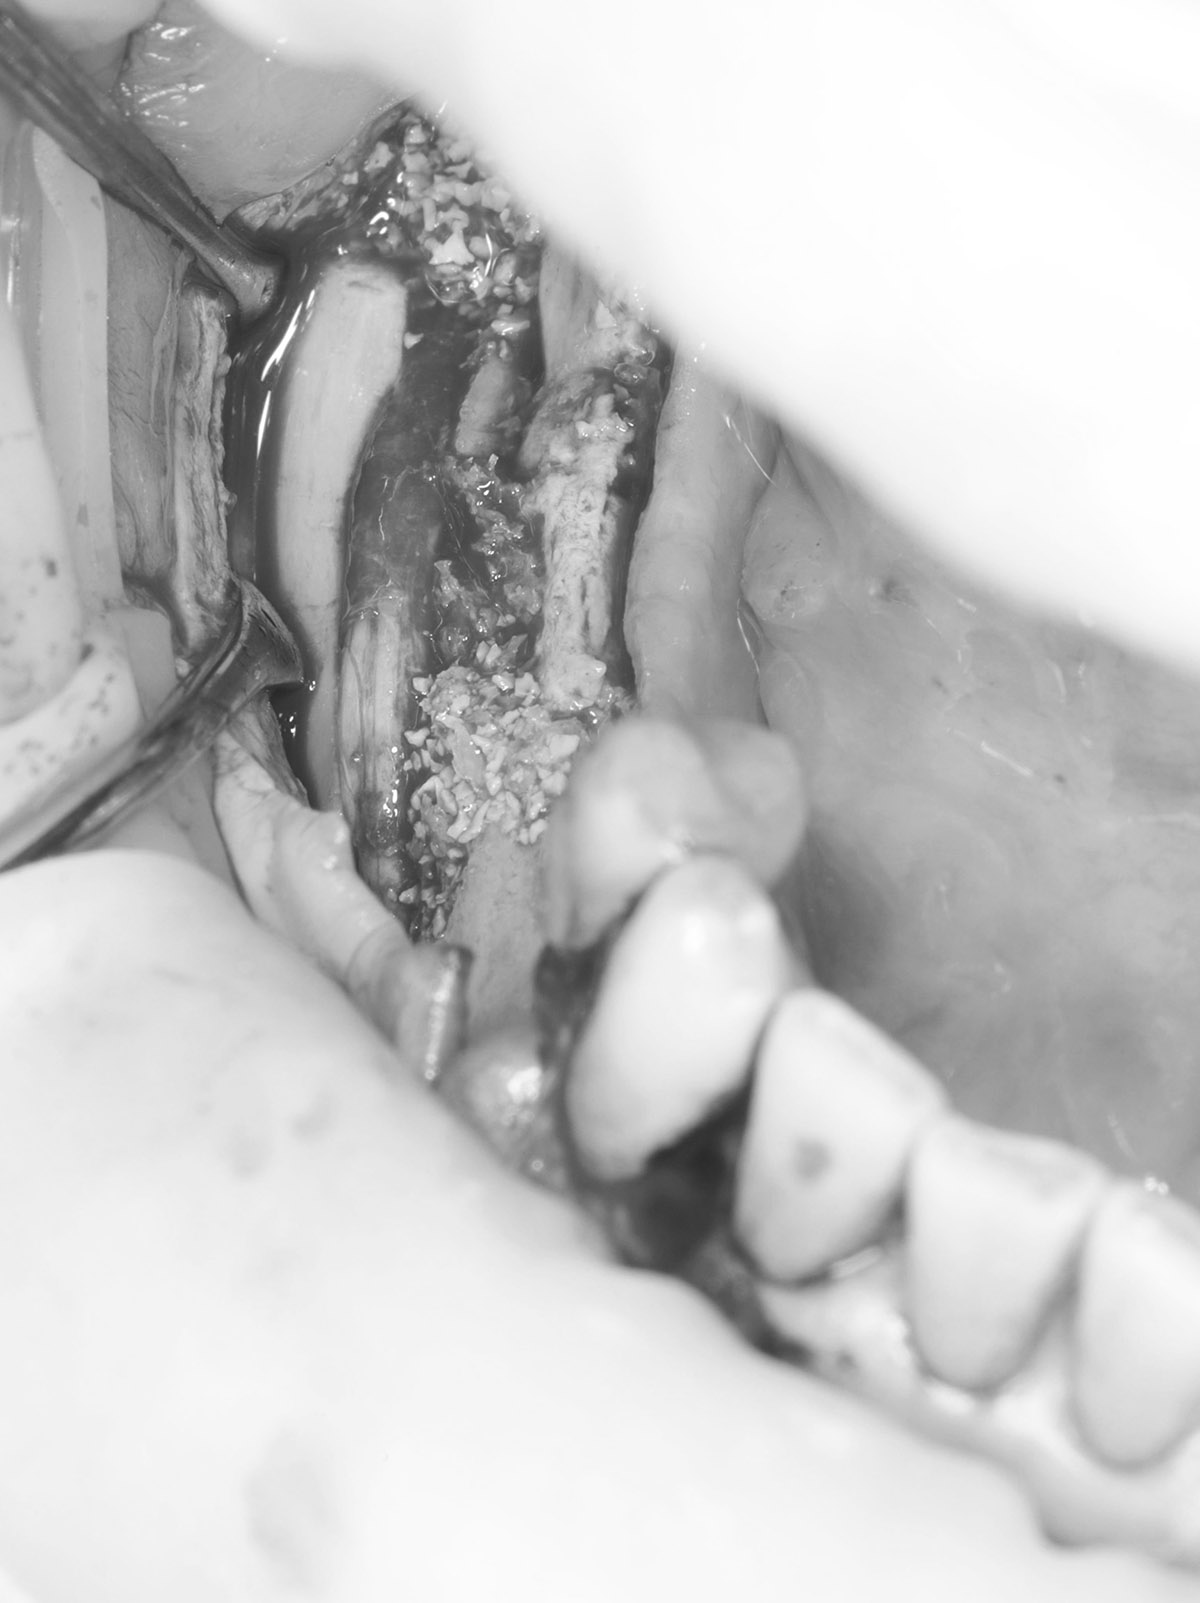

Лоскутная пластика десен является процедурой для восстановления или увеличения объема мягких тканей десен, проводимой путем переноса ткани из другого участка полости рта или с использованием донорских или синтетических материалов. Процедура помогает восстановить эстетику улыбки, улучшить защиту зубов и способствует здоровью десен. Она предусматривает тщательную подготовку, точную переноску ткани и послеоперационный уход для обеспечения успешной приживки и достижения желаемых результатов.

После коррекции десен врач закрепляет ткани швами, что стабилизирует их в новом положении и поддерживает правильную форму. Это обеспечивает оптимальное приживание трансплантированных тканей и снижает риск осложнений.